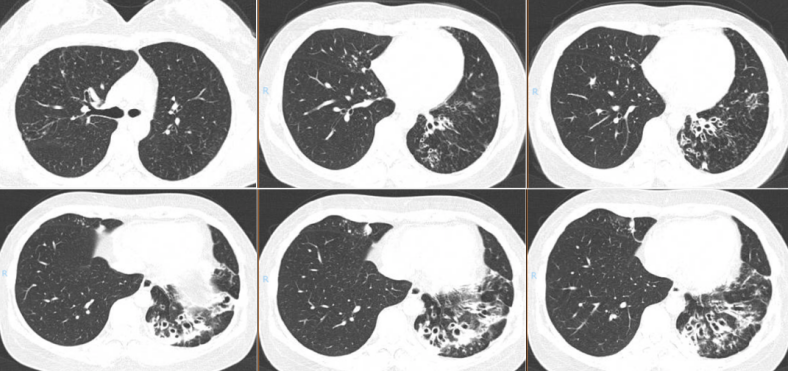

胸部CT:可见左肺下叶支扩明显,周围斑片影,感染较前增多,支气管内黏液栓增多。右肺中叶、左上肺舌段支气管管壁增厚,见点片状、斑片状影;双肺多发树芽征、小叶中心结节。